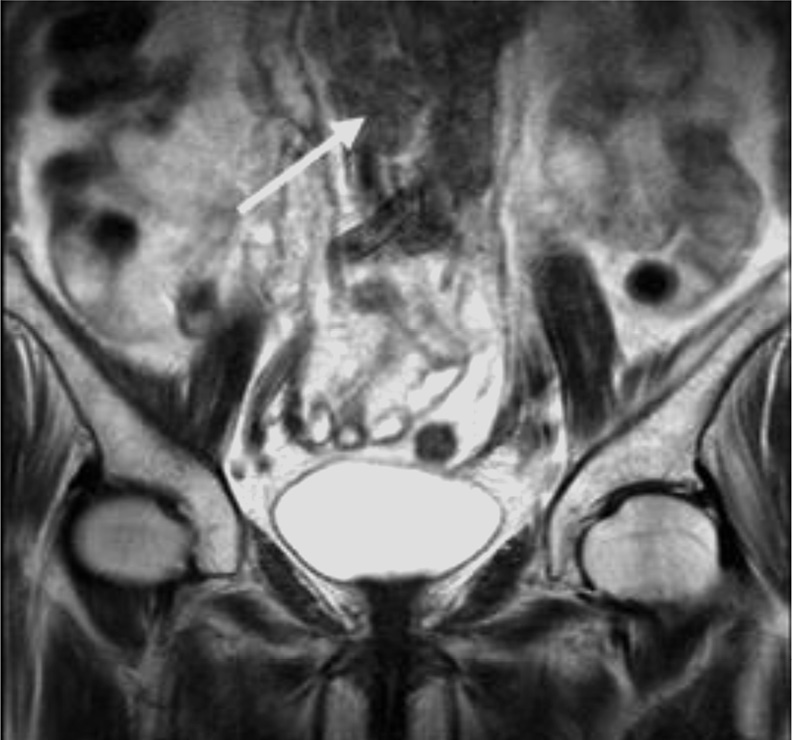

Сцинтиграфия скелета (20.10.2021): отмечены аномалии распределения радиофармпрепарата (РФП) в костях: участок повышенного накопления РФП в проекции задне-бокового отрезка VII ребра слева, участок повышенного накопления РФП в проекции заднего отрезка IX ребра слева, диффузно неравномерное распределение РФП без четких очаговых зон в костях таза и в крестце.

С целью уточнения природы выявленных аномалий и оценки распространенности поражения скелета пациенту рекомендовано выполнить совмещенную однофотонную эмиссионную томографию-КТ скелета (рис. 3).

Рис. 3. Сцинтиграфия скелета от 20.10.2021: мультифокальное метастатическое поражение костей скелета.

Fig. 3. Bone scintigraphy dated 20.10.2021: multifocal metastatic bone lesions.

Однофотонная эмиссионная томография-КТ (20.10.2021): выявленные изменения в костях таза и крестце соответствуют мультифокальному метастатическому поражению. Изменения в IX ребре слева доброкачественного генеза.